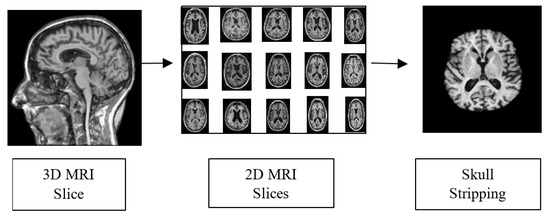

To obtain accurate classification results, preprocessing steps are necessary to prepare the input data. The raw data in Neuroimaging Informatics Technology Initiative format is used as an input for the pre-processing phase. The 3D MRI voxels are converted into 2D slices for further processing. The pre-processing operations carried out in this work are presented in Figure 6. Skull striping is performed to remove the non-brain structure and unwanted portions from the scanned image. The scalp, skull and dura from the sMRI were removed using morphological structuring. Furthermore, the dataset was split into training, validation and testing sets in the ratio 60:20:20.

Figure 6. Pre-processing Pipeline.